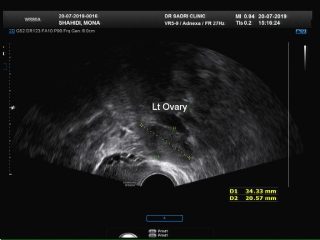

در تصویر زیر نمونه ای از خونریزی غیر طبیعی رحمی در فردی که در حول زمان یائسگی می باشد مشاهده می فرمایید:

عکس مربوط به سونو هیسترو است و در قسمت بالای کاویته رحمی تصویر یک پولیپ با پدیکل عروقی آن که از لایه قدامی اندومتر منشا گرفته رویت میشود: